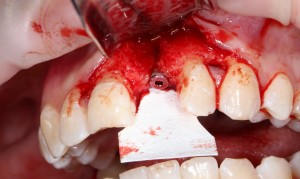

Итак, позиционируем имплантат. Для начала, с помощью пина:

Напомню правило позиционирования в области фронтальной группы зубов:

Ось импланта выходит на небную поверхность будущей коронки. Или, в крайнем случае, на режущий край.

На позиционировании имплантов делается наибольшее количество имплантологических ошибок, поэтому, если с этим есть сложности, я рекомендую использовать хирургические шаблоны. Благо, сейчас их предлагают повсеместно.

Лунка готова, устанавливаем имплантат:

Это Nobel Replace CC 3.5×13 mm. Оптимальный размер импланта для работы в этом клиническом случае.